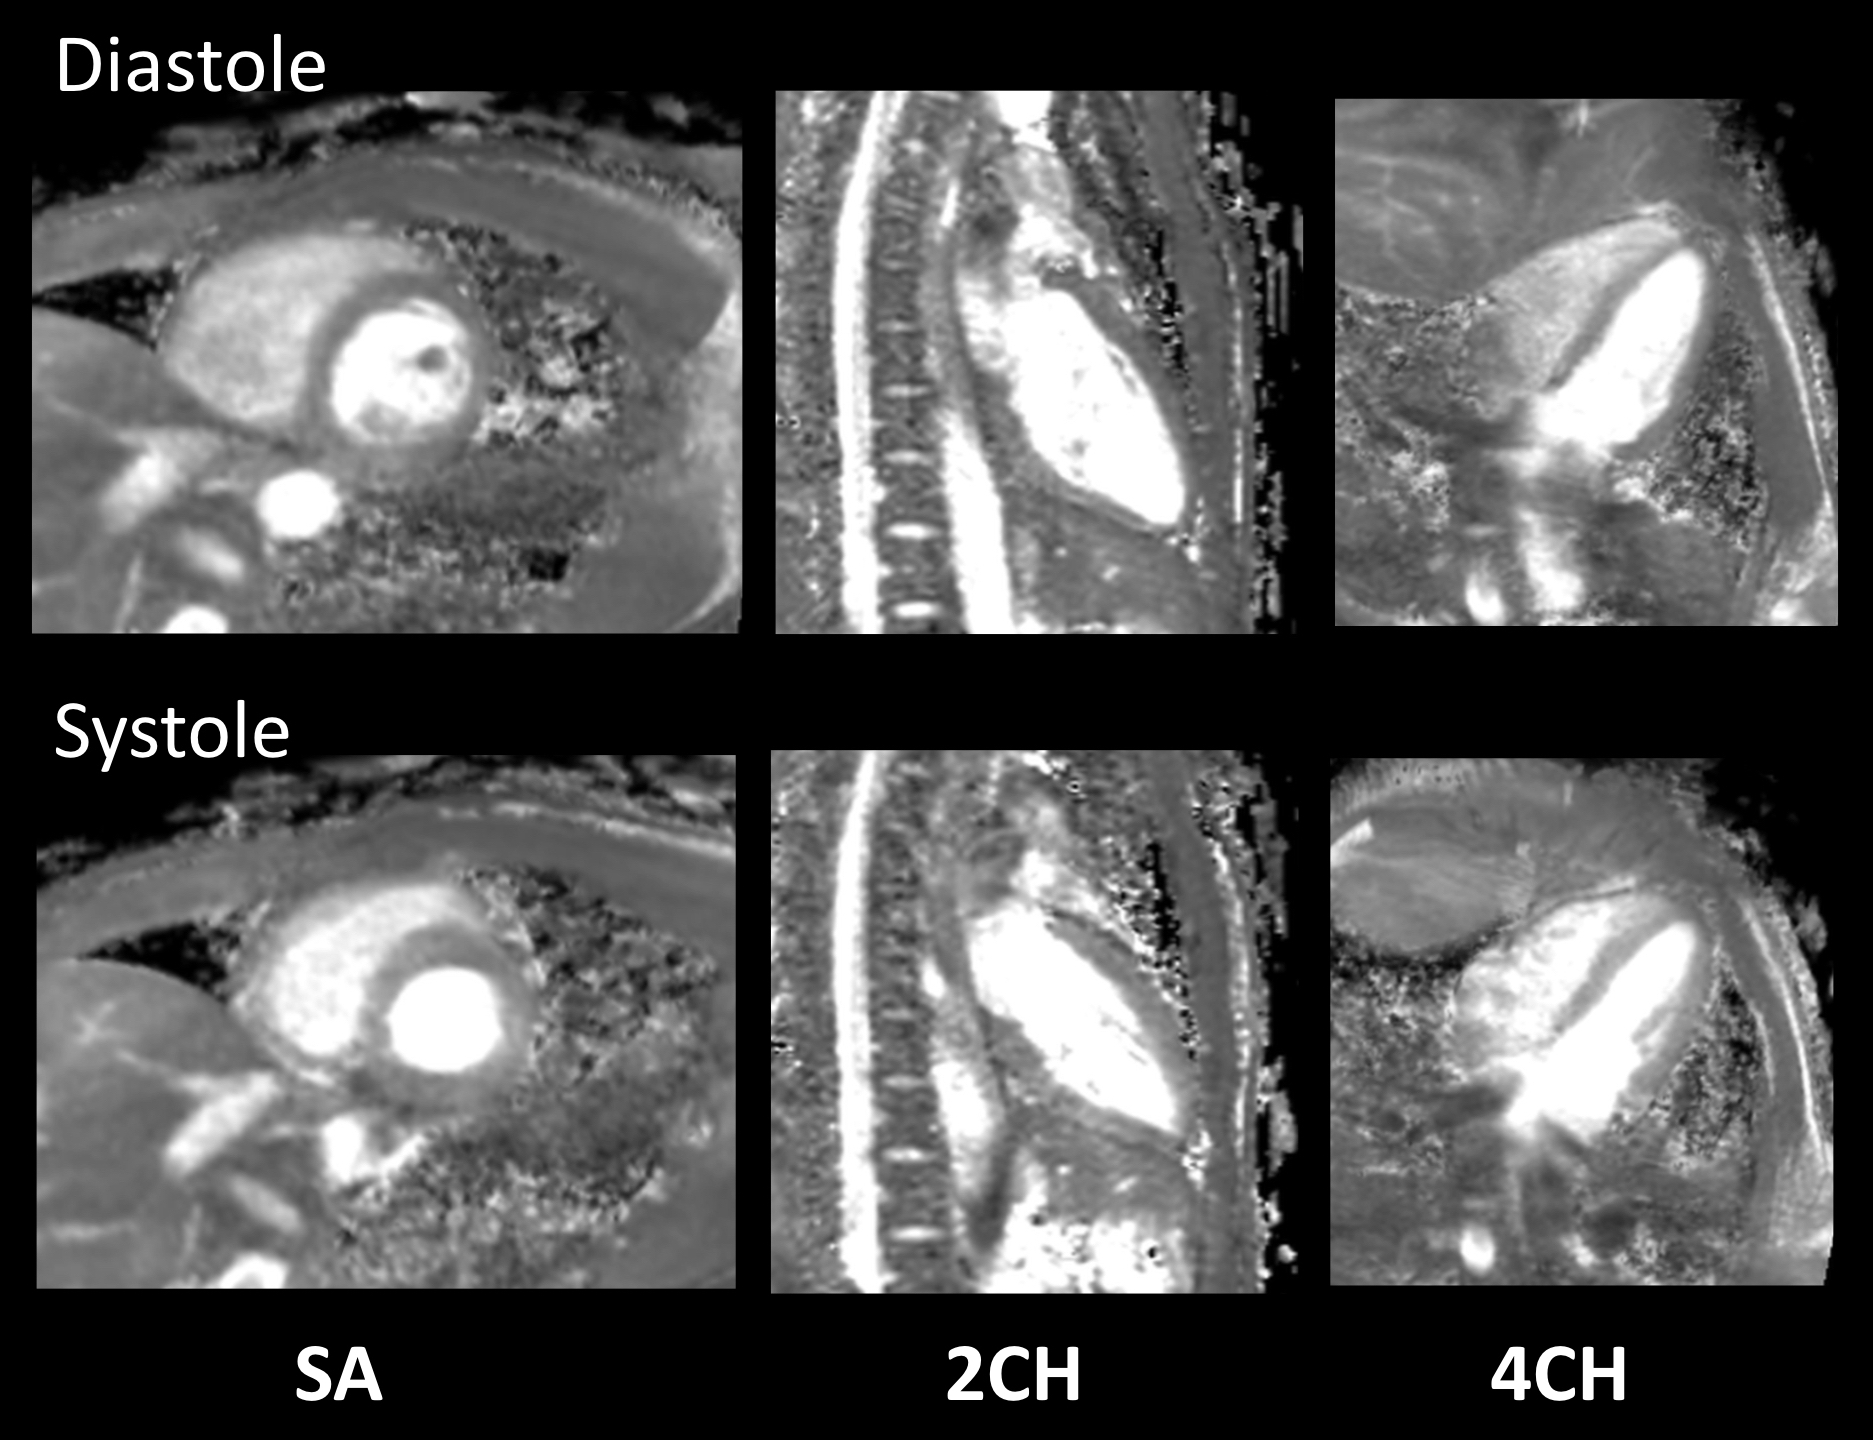

Figure 3. Representative short-axis (SA), two-chamber (2CH), and four-chamber (4CH) MPR images of 3D isotropic myocardial T2-mapping in diastole and systole.